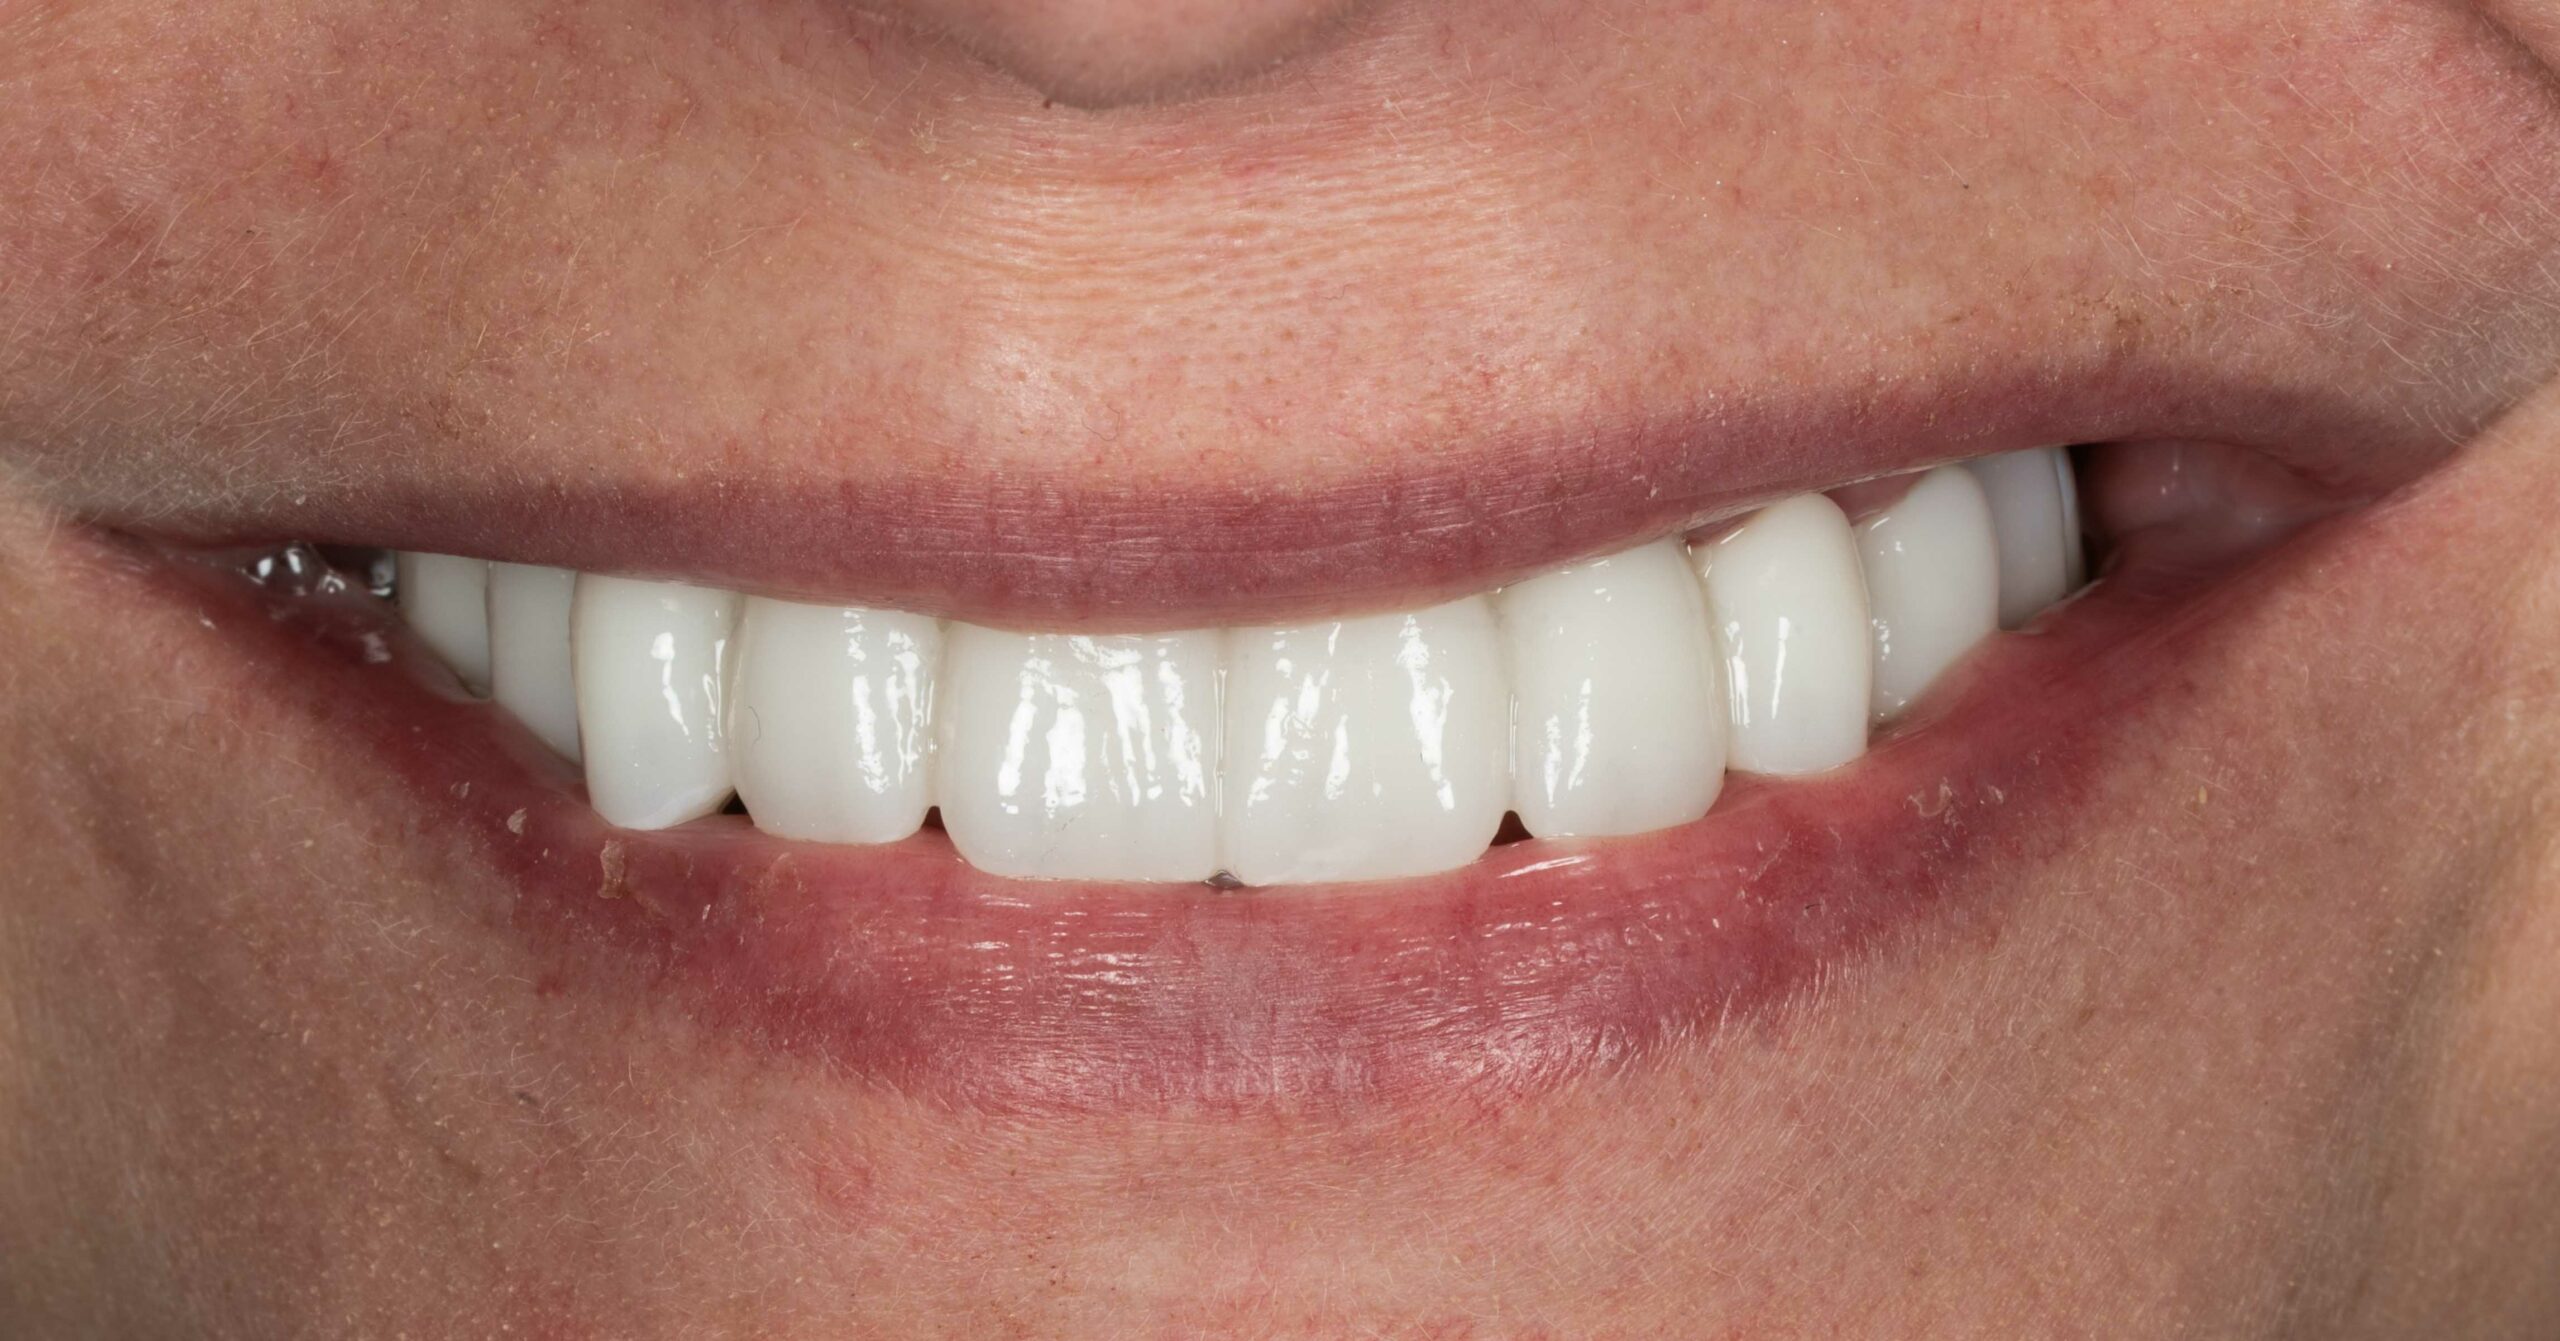

Wymiana mostu

Pacjent zgłosił się w celu wymiany mostu na zębach 21 23 odtwarzającego brak zęba 22.

Leczenie obejmowało:

- usunięcie poprzedniej odbudowy

chirurgiczną plastykę dziąsła

- wykonanie nowego ceramicznego mostu

Leczenie przeprowadził lek. dent. Kamil Kikowicz